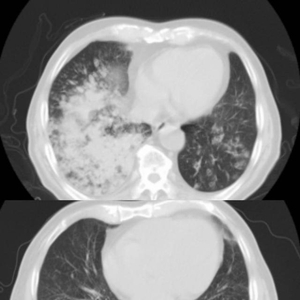

入院时,王老肺部有明显白肺。出院时间,白肺已经消失。

今年81岁的王老因咳嗽、气喘、高烧,被送至江都人民医院急诊,经查,患者指脉氧仅80%,胸部CT提示两肺有明显白肺,被收治在呼吸与危重症医学科RICU(呼吸重症监护病房)。

在医护人员的密切配合下,王老肺部的大量痰液被吸出,并成功取得所需肺泡灌洗液行NGS检测。结果显示为“肺炎链球菌及甲型流感病毒H3N2”混合感染,对症治疗后王老告别了咳嗽、气喘,影像结果显示白肺也已消失,王老于上周顺利出院。